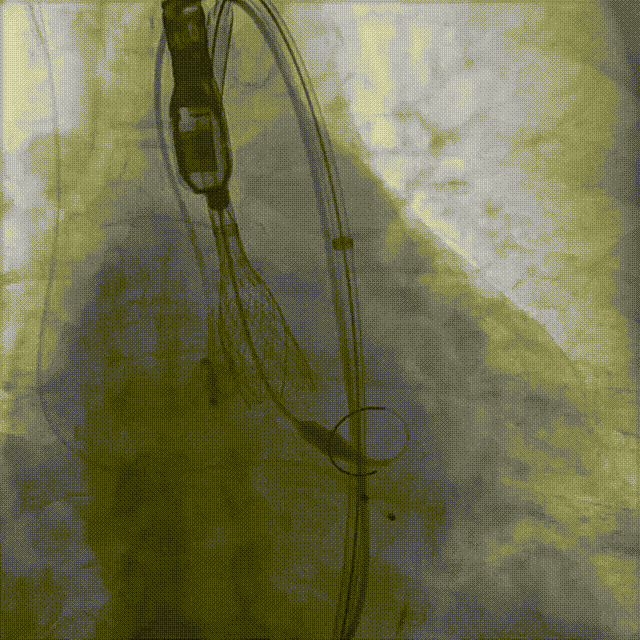

患者病史 体检发现心脏瓣膜病半月余,平素无症状 ,有高血压病史。 后来院复查诊断为:主动脉瓣狭窄(重度)、先天性主动脉瓣二叶瓣畸形、心室肥厚、升主动脉扩张心功能 I 级(NYHA 分级)、高血压病 2 级(极高危)。 术前 CT:Type0型二叶瓣,瓣叶增厚,无钙化,类风湿性;瓣环径25.6mm,LVOT稍收窄,瓣环水平夹角66.6°,轻微横位心;左右冠开口高度可,瓣叶不长,无冠脉风险;心室收缩末内径约32mm,室壁增厚;外周入路无明显迂曲,无钙化、双侧内径可、双股中分叉,右侧为主入路能够支持20F大鞘通过。 造影角度及入路:LAO 6° CAU 13° 手术策略 采用右侧股动脉为主入路,左侧为辅助入路,常规穿刺。推荐使用20球囊预扩,预装TAV29瓣膜,初始定位对齐瓣环上0mm开始释放。 手术过程 20号球囊预扩无明显腰征 输送器过弓跨瓣顺滑 80%工作位观察 术后造影,瓣膜释放位置良好,无瓣周漏 术后超声:人工生物瓣释放后形态满意,瓣叶开放、关闭活动良好,无瓣周漏;跨瓣血流速度降至 2.5m/s,平均压力梯度6mmHg,符合手术预期。 Prostyle A®预装干瓣——“刚柔并济”助力临床最优化解决方案: 丝滑过弓能力:Prostyle A®短瓣架设计联合远端超滑亲水涂层,即使没有联合使用snare,都可以柔顺过弓,该例横位心的患者更好的展现了输送系统的柔顺性; 平衡的径向支撑力:该例患者Type0型二叶瓣,术后形态展开良好且无瓣周漏,在横位心等复杂情况下实现稳定锚定。 80%可回收设计:80%工作位观察,起搏时间更短,对患者损伤减少到最小,也利于术中精准调整瓣膜位置,保证术后效果。

患者病史 男性,74y, 因 “发现心脏瓣膜病 1 年,加重伴喘气半年” 入院。门诊检查显示主动脉瓣重度AS并伴轻-中度AR。患者基础疾病较多:胸腹主动脉多发穿透性溃疡、心功能III级等,手术指征明确,但风险极高。 术前CT LVOT- Annulus 倒梯形,对植入瓣膜有挤压位移风险,Annulus直径23.7mm,瓣叶增厚,钙化集中在无冠窦边缘。 左冠脉开口高度可,瓣叶不长、窦部空间较大,无冠脉风险;室间隔膜部较短,有一定PPI风险,心脏角度37.9°;心室较小,有一定循环崩溃风险,术前注意补液。 术前造影角度及入路:血管入路散在钙化、无迂曲;主动脉弓条件好、双侧股动脉直径大、右股穿刺点侧壁存在环形钙化 左右重合位:RAO 7° CAU 21° 右窦中心位:LAO2 1° CAU 1° 手术策略 20mm球囊预扩后植入AV26瓣膜,同时做好预防循环崩溃、传导阻滞的应急预案。 术中挑战 1)球囊预扩:20mm球囊预扩时无明显 “腰征”,但存在少量反流,提示瓣膜钙化与解剖结构对扩张的阻力不均 2)首次释放偏差:第一次定位释放时,瓣膜在 “开花” 过程中下滑约 3mm,工作位观察显示小弯侧瓣周漏较多(深度超过完全覆膜区),需二次调整。 3)二次精准定位:以猪尾导管为参照,将定位点调整至 “猪尾 - 2mm” 处,结合真实窦底深度(较深)重新释放,最终瓣膜位置稳定,瓣周漏显著减少。 术后即刻效果: 瓣膜形态良好,跨瓣压差从术前的 67mmHg 降至 6mmHg,且无明显瓣周漏,冠脉开口通畅; Commisural Alignment 术后即刻超声: Prostyle A®预装干瓣——助力临床最优化解决方案: √ 平衡的径向支撑力:特殊的解剖结构下位置形态良好,术后跨瓣压差大幅降低,血流动力学改善明显; √ 80%可回收设计:支持术中二次调整释放位置,保证精准释放; √ 平衡的收腰设计&Commissural Alignment设计: 为患者后期冠脉PCI保留了生命通道;